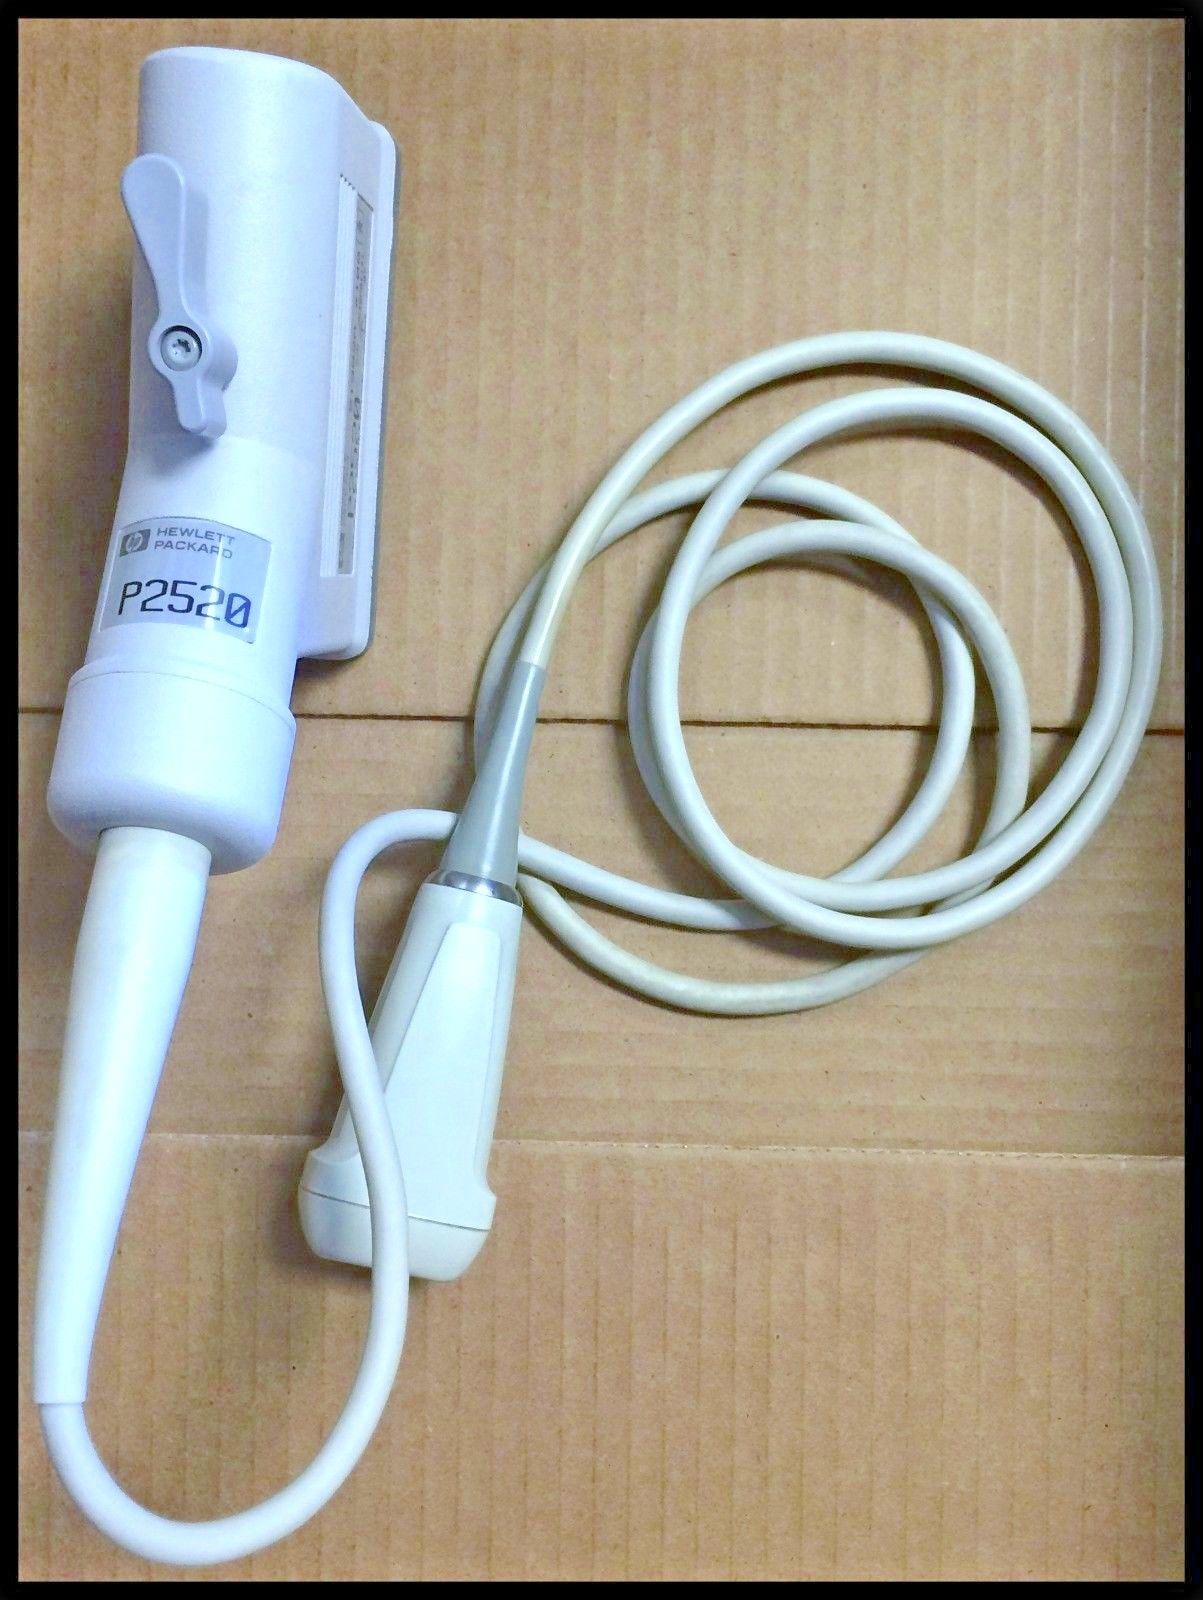

PHILIPS S5-1 SECTOR ARRAY ULTRASOUND PROBE

Sale price$ 6,148.36